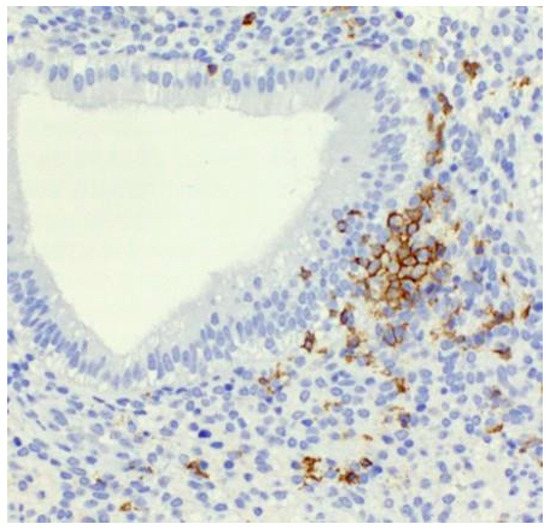

Clustering of Uterine Natural Killer Cells Around Uterine Glands in Women with Recurrent Implantation Failure and Recurrent Pregnancy Loss: An Immunohistochemical Study

by Lenka Lapides, Martin Klein, Ivan Varga, Jaroslav Voller and Pavel Babal

Int. J. Mol. Sci. 2025, 26(20), 10109; https://doi.org/10.3390/ijms262010109 - 17 Oct 2025

The immunological factor of sterility, specifically the abnormal count and activity of uterine NK (uNK) cells, may represent one of the potential contributors affecting specific subgroups of sterile couples undergoing assisted reproductive treatment (ART). Therefore, the primary purpose of the present paper was [...] Read more.

The immunological factor of sterility, specifically the abnormal count and activity of uterine NK (uNK) cells, may represent one of the potential contributors affecting specific subgroups of sterile couples undergoing assisted reproductive treatment (ART). Therefore, the primary purpose of the present paper was to assess uNK cell count. A total of 387 endometrial biopsies from patients with recurrent implantation failure (RIF) or recurrent pregnancy loss (RPL) were analyzed to identify abnormalities in uNK cell count, using immunohistopathological evaluation. ANOVA analysis revealed a strong association with factor 0.161 with p-value < 0.01, indicating that higher uNK cell count is associated with the presence of clusters (multicellular aggregates of uNK cells). These results suggest that the formation of clusters and the spatial distribution of uNK cells are significant factors in the context of the aforementioned clinical questions. However, the actual translational potential to clinical practice has not yet been established due to several challenges, namely: 1. the constantly changing definitions and diagnostic criteria for RIF and RPL, 2. varying sampling approaches for uNK cells, and 3. the historical lack of clear differentiation between uterine and peripheral NK cells. When all these issues are resolved, the observed tendency of uNK cells to form clusters will need to be a central focus of future investigations addressing RIF and RPL, thus improving ART outcomes. Full article